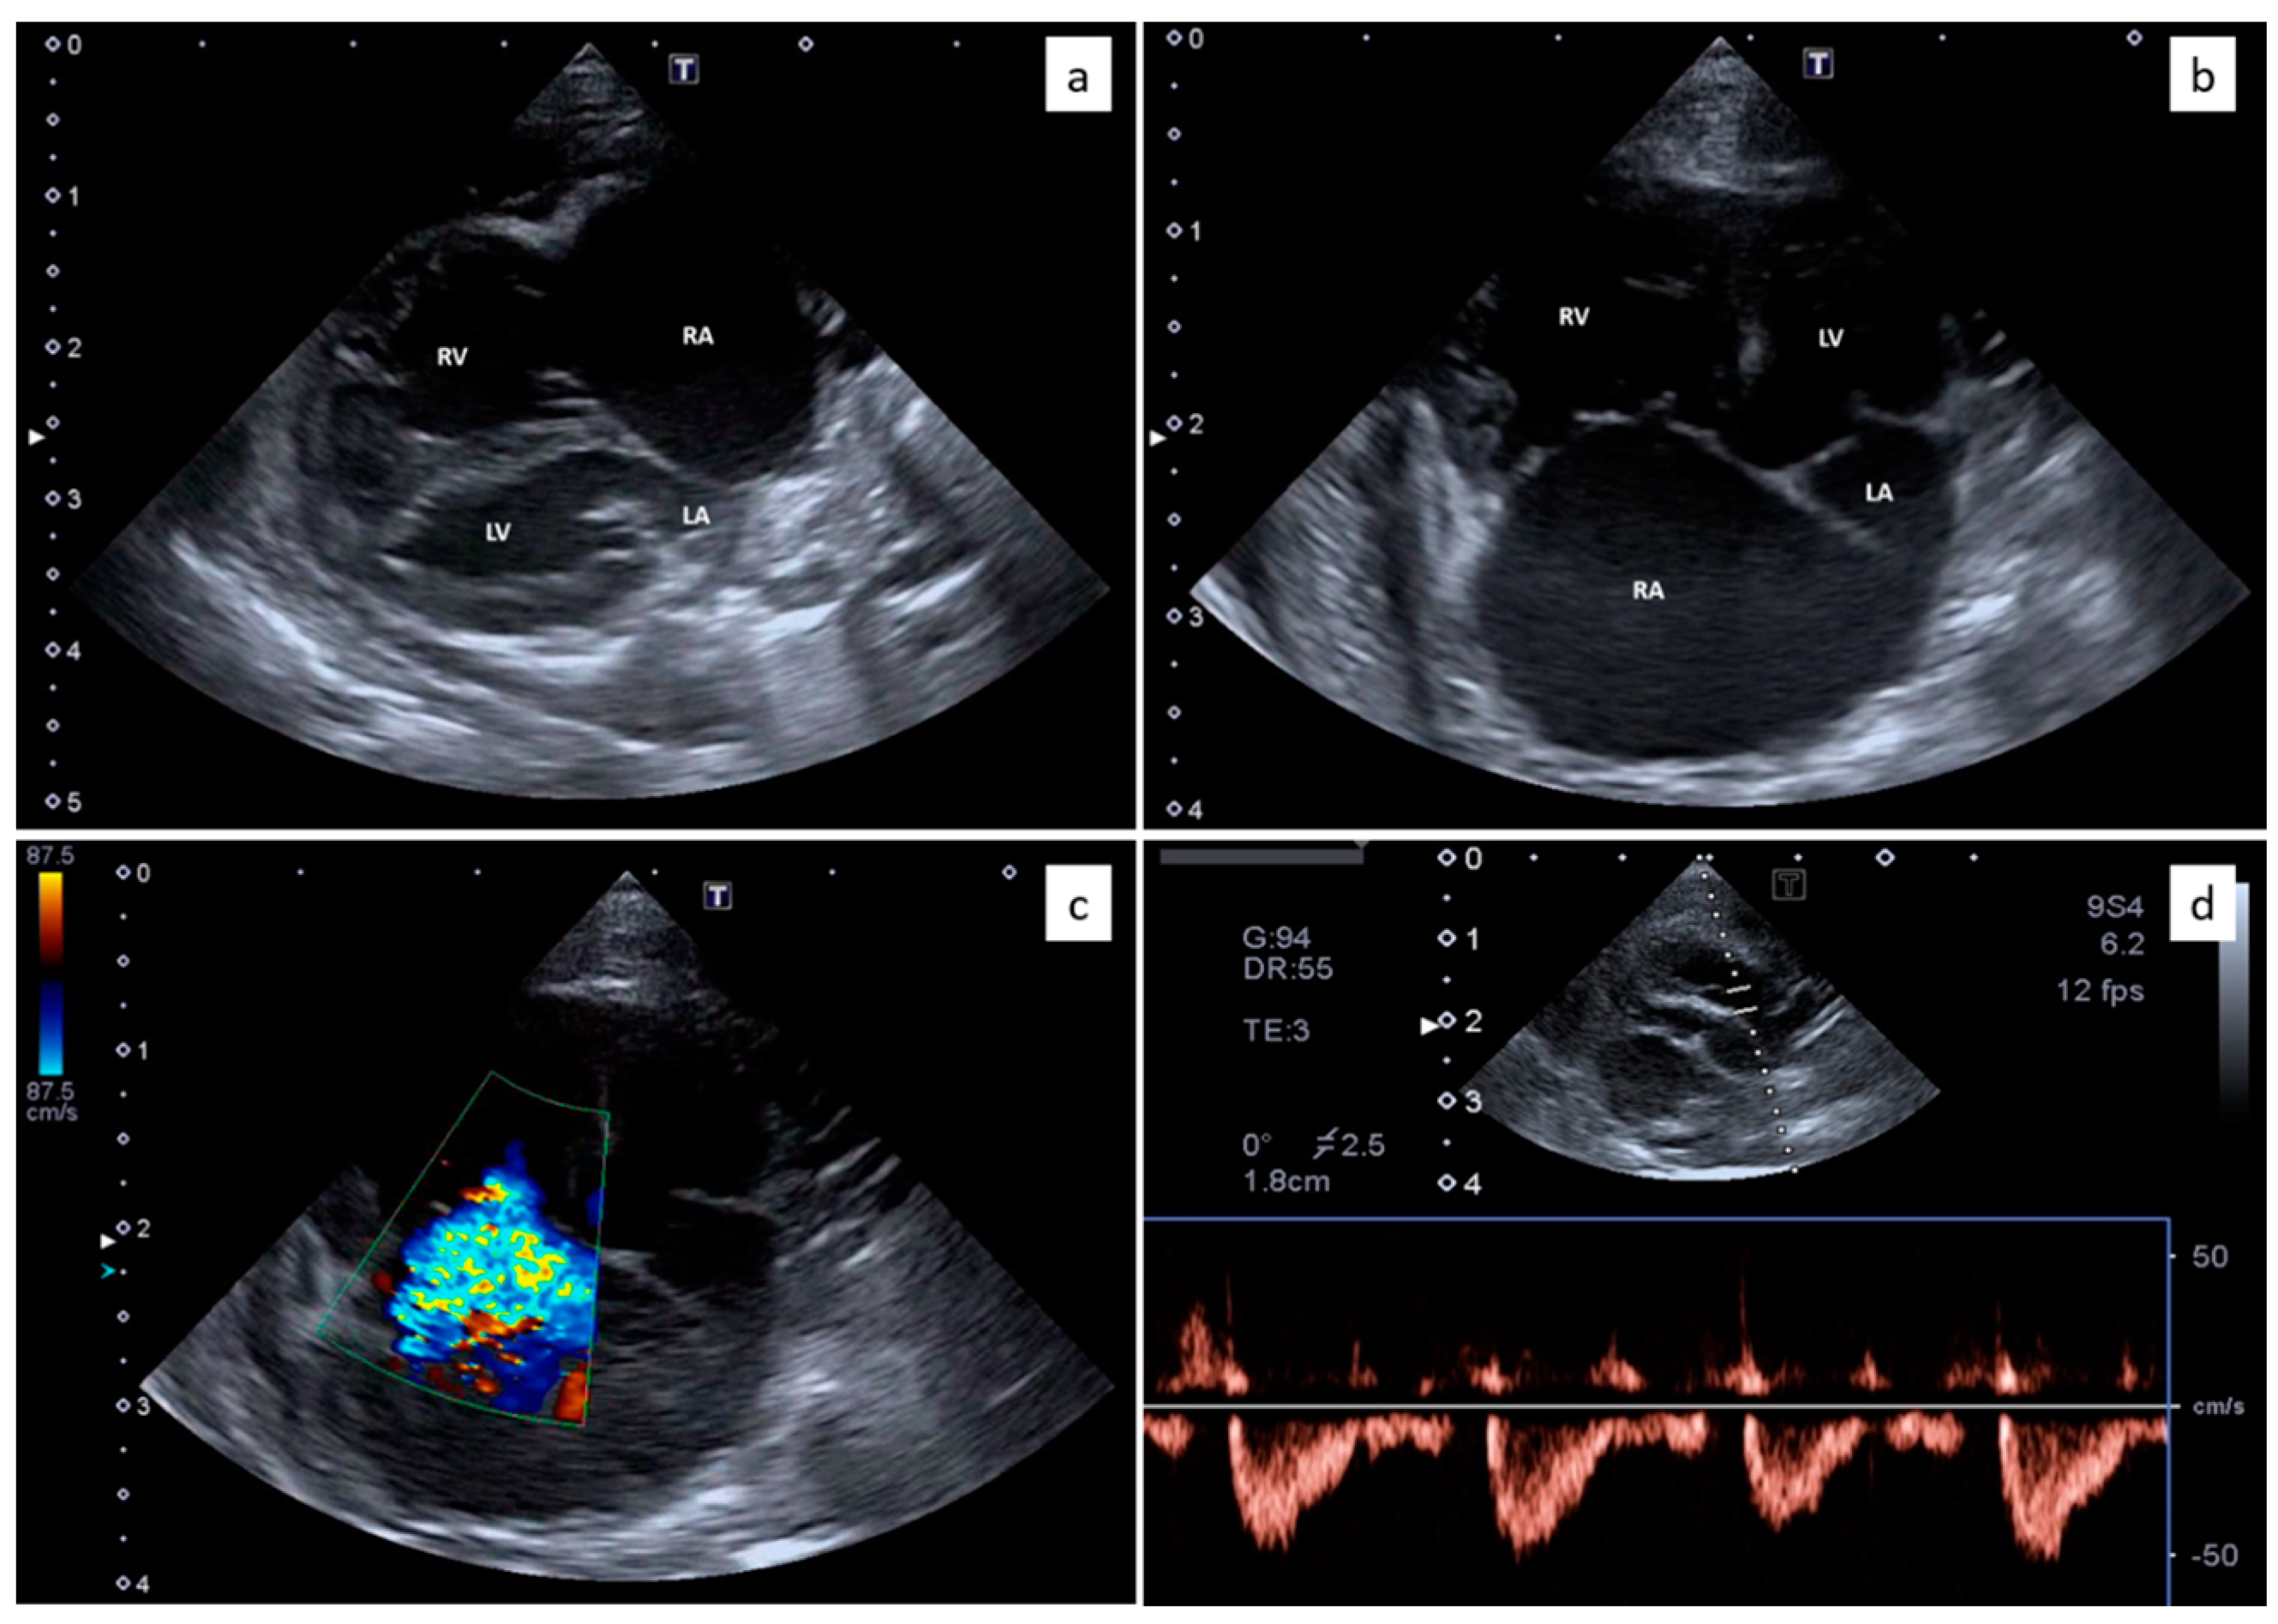

Thoracic radiographs showed a diffuse interstitial and alveolar pattern, with mild pleural effusion (Figure 1). The increased sternal contact of the cardiac silhouette suggested right-side cardiomegaly.

Figure 1.

Thoracic radiograph (lateral view) from a 6-month-old domestic kitten with progressive dyspnoea. Diffuse interstitial and alveolar pattern, with mild pleural effusion, was evident. The increased sternal contact of the cardiac silhouette suggested right-side cardiomegaly.